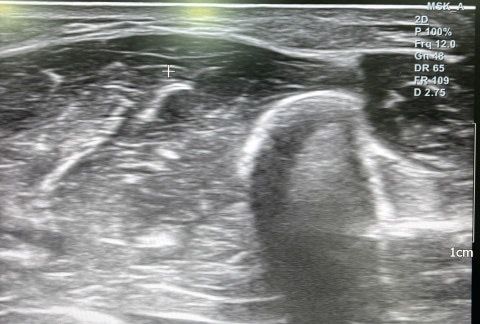

해당 사진은 병원에서 찍은 초음파이고 의사 분께서는 지방종이니 수술을 원하면 없앨 수 있다고 하셨는데 지방종이 맞을까요?

해당 종양은 3년 정도 전에 생겼고 팔에 2개 정도가 5센치 간격으로 동그란 공처럼 만져집니다

초음파만으로 확정 진단을 말하기는 조심스러우나, 제공하신 이미지와 설명을 근거로 보면 의사가 지방종(lipoma)이라고 판단한 흐름은 타당한 편입니다.

1. 초음파 소견상 지방종이 의심될 때의 특징

피하층(subcutaneous fat) 내부에

주변 지방과 유사한 밝기(저에코~등에코) 구조가 보이고

비교적 균일하게 층층이 보이는 섬유격막(striation) 이 관찰됩니다.

현재 사진에서도 피하층 내에 그런 패턴이 보여 지방종과 어느 정도 일치합니다.